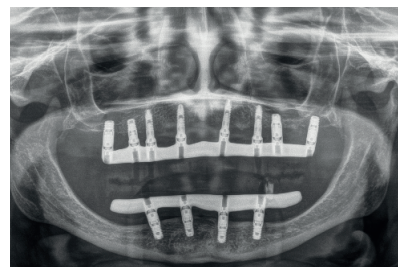

Una vez finalizada la confección de la prótesis, se coloca en el paciente. En las imágenes podemos observar el resultado clínico final y la radiografía, donde puede verse el ajuste de las estructuras sobre los implantes (Figuras 24-26).

Podemos observar la comparación entre el estado inicial y el resultado final, que satisface los deseos estéticos y funcionales de la paciente y además recupera la dimensión vertical perdida con las prótesis removibles (Figuras 27-30).